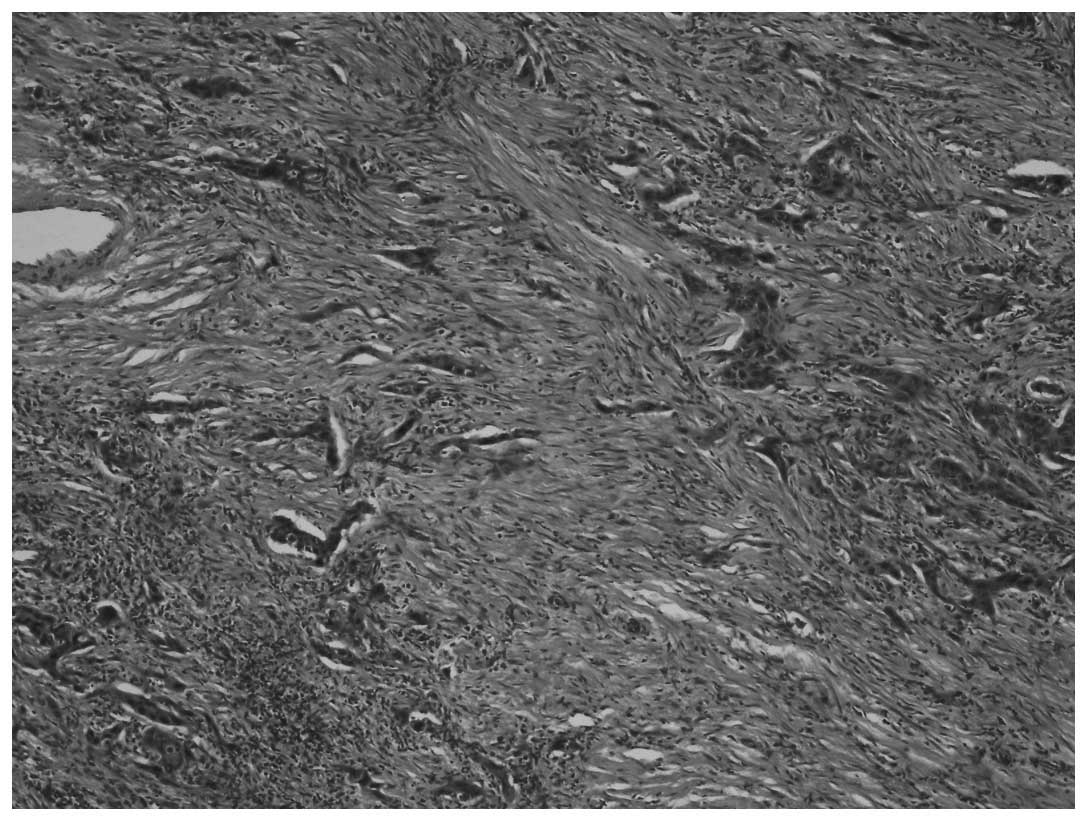

On macroscopic examination, the nephroureterectomy specimen included the left kidney, measuring 18×13×8 mm, a ureteral segment 190 mm in length and a ureteral calculus measuring 25 mm in diameter. The thickness of the renal cortical parenchyma was reduced to 1 mm. Three nodular lesions with irregular margins, brown to dark yellow in color were identified in the kidney, with the largest of the lesions measuring 30 mm in diameter. The total diameter of the nodular lesions was 70 mm. The microscopic examination of the lesions revealed tumor cells with fusiform nuclei and a pink cytoplasm, exhibiting diffuse pleomorphism and areas of necrosis. The mitotic count was 19–20/10 high-power fields. Islands of carcinomatous cells were identified, embedded in a desmoplastic stroma [hematoxylin and eosin (H&E) staining; magnification, x40; Fig. 1]. Sarcomatous areas, composed of pleomorphic fusiform cells with marked atypia were also identified (Fig. 2) (H&E staining, magnification, x40).

Figure 2

Marked pleomorphism with atypia, spindle cells and sarcomatous areas. Hematoxylin and eosin staining (magnification, x40).